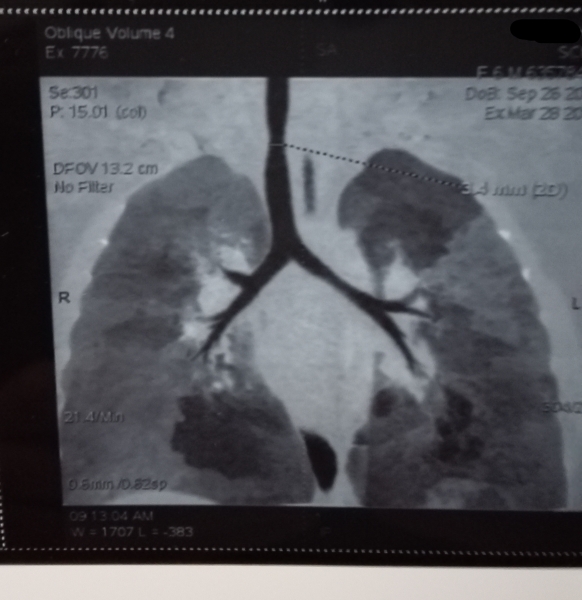

检查日期: 2016-03-24

宝宝出生前彩超提示室缺,考虑比较小,就没有处理,出生后40天因为家人感冒传染后患肺炎,住院治疗后好转,2月大的时候再次因为家人感冒传染后患肺炎,比第一次重,喘息,有哭闹时间长了有紫绀,治疗好了后3月大的时候去了贵院UCG检查:室缺9mm,膜周融合型,分流弥散,左向右分流2.22m/s,肺动脉瓣轻度狭窄,肺动脉高压40.4mmHg,考虑年龄太小没有手术。随后一直未再肺部感染,呛水后有点喘息,几分钟好转,偶有咳嗽。2016年3月份半岁的时候再次前往贵院检查:彩超基本差不多,CT检查:VSD,气管中段狭窄,3.4mm,本来都住院了,但是住院部主任看了后说暂时不能手术,让回来等大点检查再说。请陆医生帮忙看看,什么时机手术最好,非常着急,求解答,谢+ T( A, ]1 K. i) y